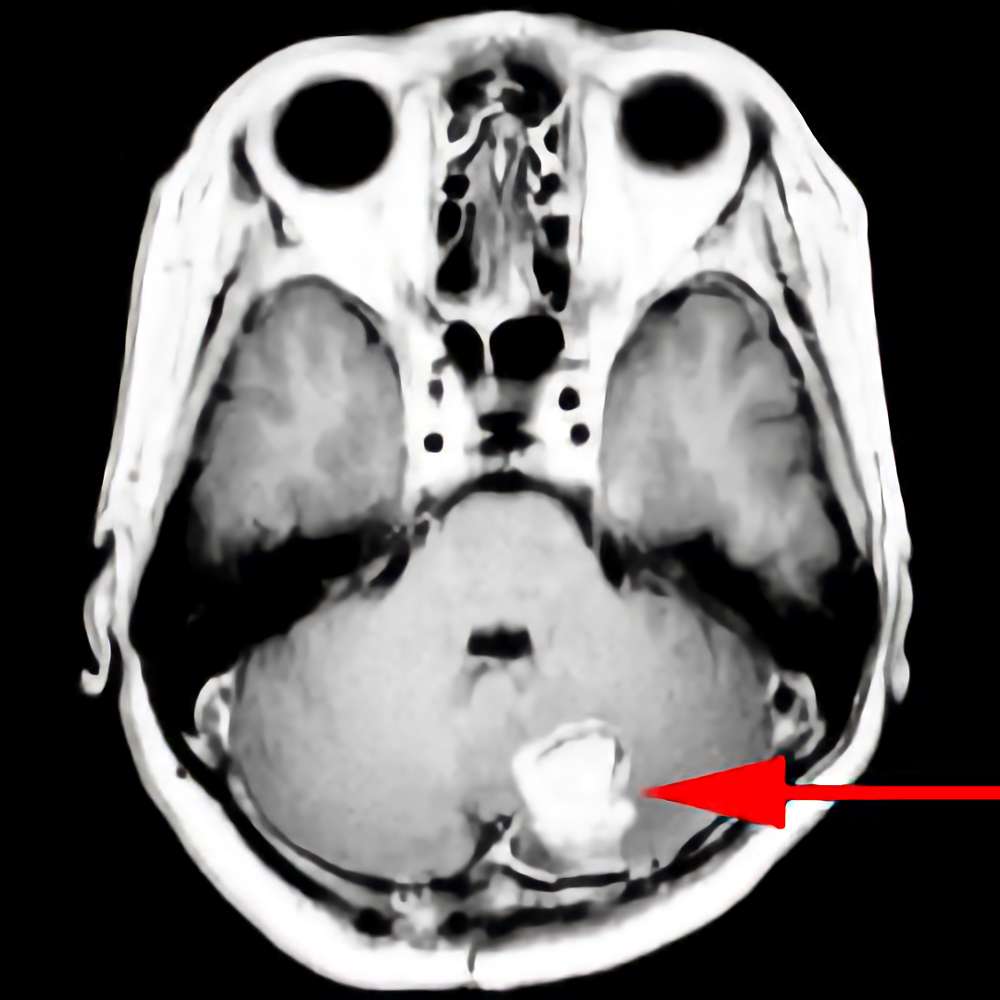

346

'22年11月

60代

後頭蓋窩腫瘍

頭蓋内腫瘍摘出術

No.’22_103 手術前1

No.’22_103 手術前2